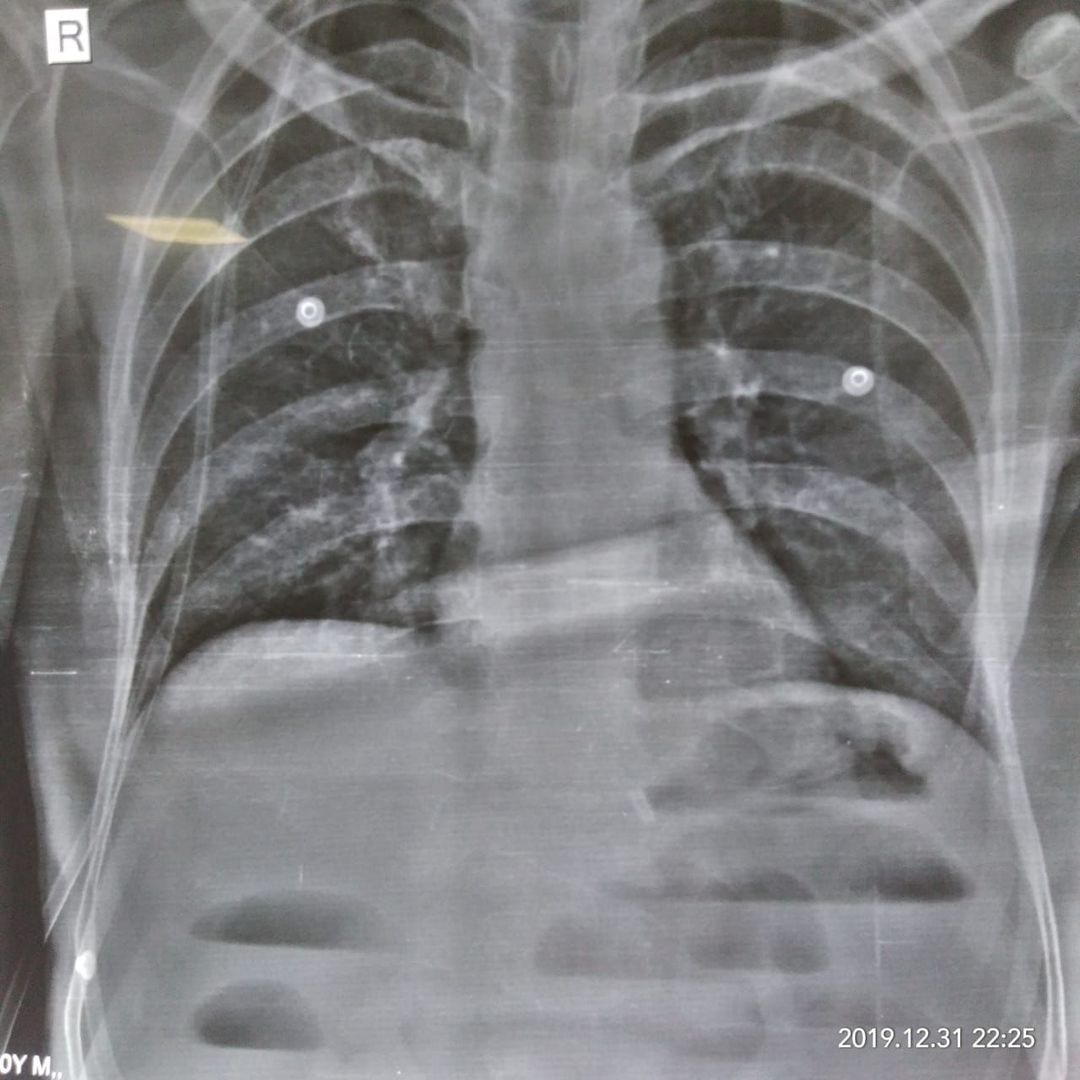

What is the diagnosis?

Multiple air fluid level in intestinal obstruction

Small intestine occlusion ?